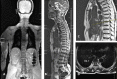

Methods: We report 2 unique cases of distal junctional failure (DJF) with worsening of neurology, secondary to nontraumatic fracture of a lower instrumented vertebra operated for thoracic canal stenosis without deformity. The first case had acute worsening of the Neurology during follow up and on evaluation, the supine CT and MRI scan revealed well decompressed spinal canal, no implant migration to the canal, no screw loosening, or rod failure. Supine sitting radiographs demonstrated DJK with Fracture and the patient underwent extension of fusion till the pelvis with 3-rod construct and interbody fusion, because of the instability at the L1 level.The second case remained neurologically stable for a month and then had an acute onset of back pain, sensory deficit, and urine incontinence. The supine-sitting dynamic radiograph done demonstrated L1 fracture with DJK at D12-L1 levels. The patient was counseled for extension of fusion, which was deferred by the patient.

Results: Patients in our series, had an acute worsening of neurological deficit within a month of posterior spinal fixation. Their supine imaging was almost normal, and the diagnosis of DJK with L1 fracture instability was possible only on a supine-sitting dynamic radiograph. Various factors like obesity, TL kyphosis, osteoporosis, etc. can be the attributing factors for the development of DJK CONCLUSION: A high index of suspicion is required for diagnosing nontraumatic fracture in long-level fusion patients with acute neurological worsening. The supine-sitting dynamic radiograph is an important diagnostic tool for DJF in patients having difficulty standing erect.